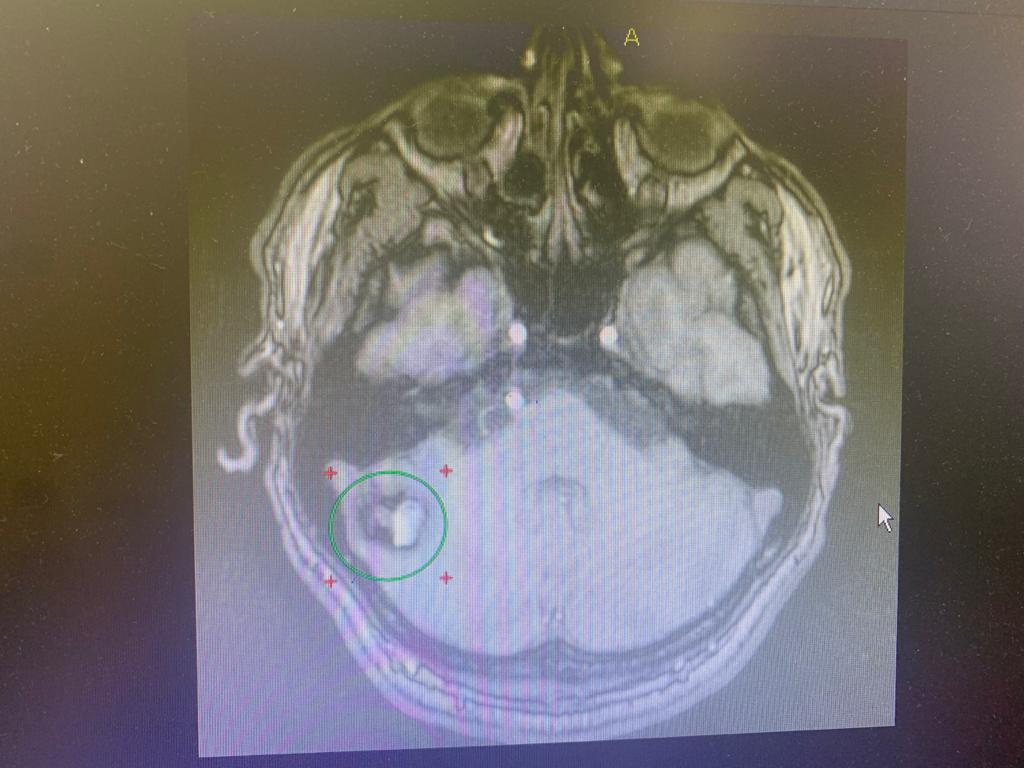

Были назначено полное обследование пациента. На МРТ головного мозга выявлена кавернома правого полушария мозжечка,  имелись признаки перенесённого кровоизлияния. Учитывая хирургическую доступность к каверноме, нейрохирурги клиники выполнили операцию, пациент при этом находился в положении сидя.

Кавернома удалена тотально.